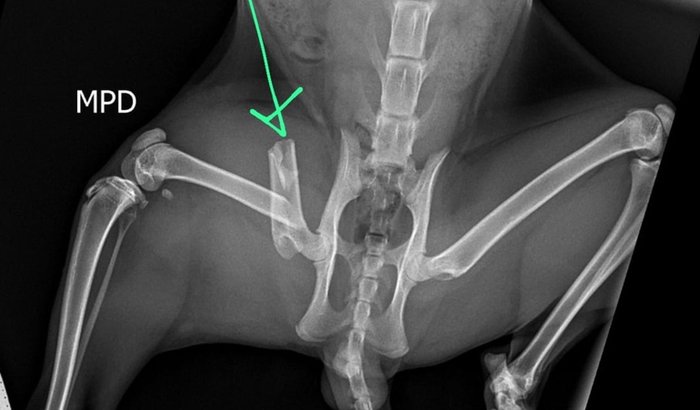

Conheça o Gemada, O gatinho Gemada foi abandonado aqui na rua de casa, dentro de um saco de ração... Fazia uma semana que estamos tratando ele, quando ele sumiu.. No sábado, dia 25/10, ele desapareceu e nos deixou em horas de muita angústia e preocupação. No domingo, 26/10, recebemos a alegria de tê-lo de volta… mas, infelizmente, descobrimos que sua patinha traseira estava quebrada. 💔 Na segunda-feira, 27/10, ele passou por cirurgia e agora segue em recuperação, precisando de cuidados especiais.